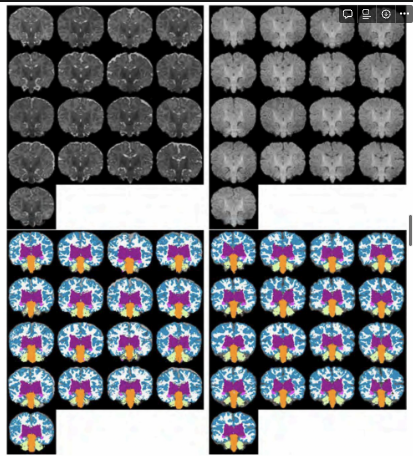

MANTIS 분할 비교

좌상단 : T2w 입력이미지 좌하단 : T2w MANTIS 분할사진

우상단 : T1w 입력이미지

우하단 : 우리 솔루션을 통해 왼쪽/오른쪽 반구 레이블을 함께 그룹화해 segment한 결과